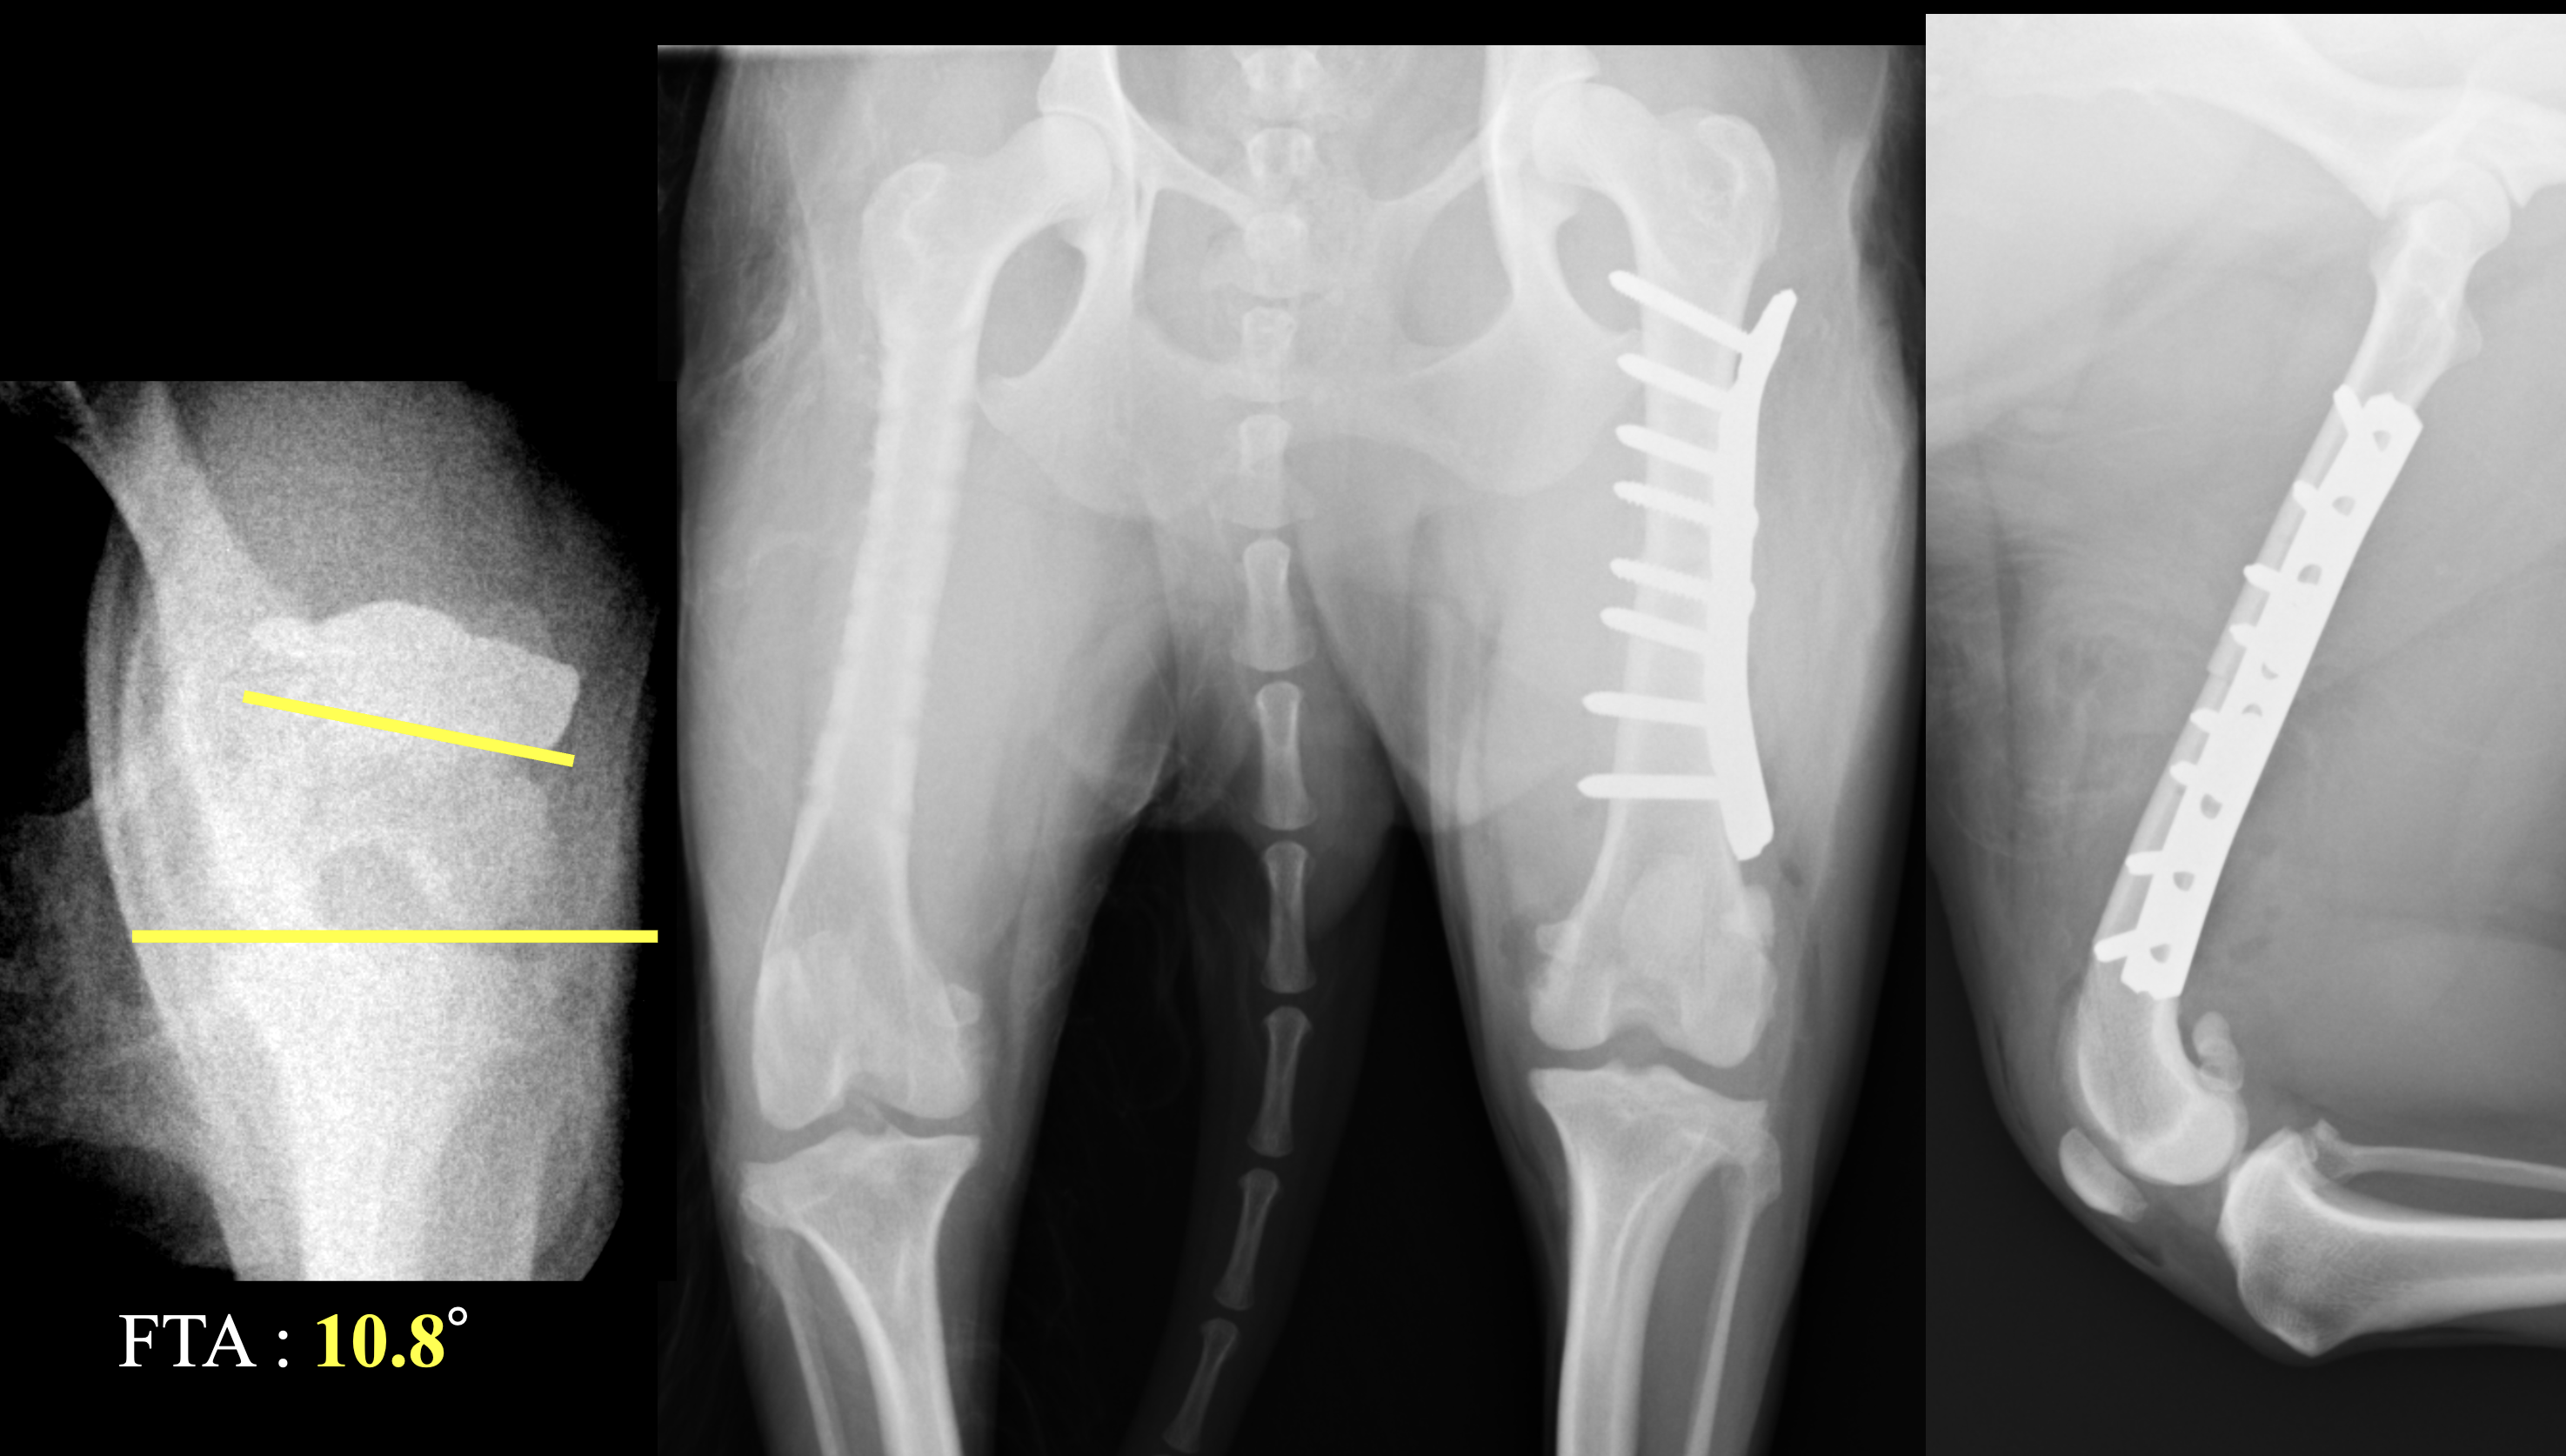

膝蓋骨外方脱臼(LPL)は小型犬では少なく、全体の10%以下と言われています。また、犬のLPLの治療は特に大型犬では成功率は非常に低いという報告があります。一方で、小型犬でのLPLの治療に滑車溝形成術、脛骨粗面転移術、軟部組織の手術を行なったところ、治癒率は高かったという報告もあります。現在のところ、小型犬膝蓋骨外方脱臼に対する報告は少なく、その治療方法は個々の獣医師の裁量に委ねられているところがあります。今回、小型犬の両側膝蓋骨外方脱臼(LPL)に対して、大腿骨前捻角矯正を行なったところ、治療が奏功した1例を紹介します。 症例はスピッツ、避妊雌、5歳1ヶ月齢、6.8kgです。既往歴は保護犬のため不明です。両後肢ともに曲がってしまっており、歩き方がおかしく、段差を降りることができないという主訴で来院されました。

今回前捻角を矯正したことでLPLは正常な位置に固定され、順調な経過を経ることができました。まだLPLに関しては情報が少なく、ベストな治療法が確立されていませんが、CT検査などにより本人の状態を正しく理解し異常を検出することが重要であると考えます。MPLと異なる病態であることを理解して治療にあたることも重要です。